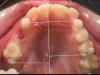

Девочки,сняли сегодня аппарат Марко Росса. Результат за пол года . Теперь весной брекеты ,либо элайнеры 2*4,либо ждем смены Зубов и ставим полноценные на весь рот ,будет понятно после КТ в феврале. Результатом на данный момент мы очень довольны 👍 фото в коментах) первые фото ДО,рядом после.